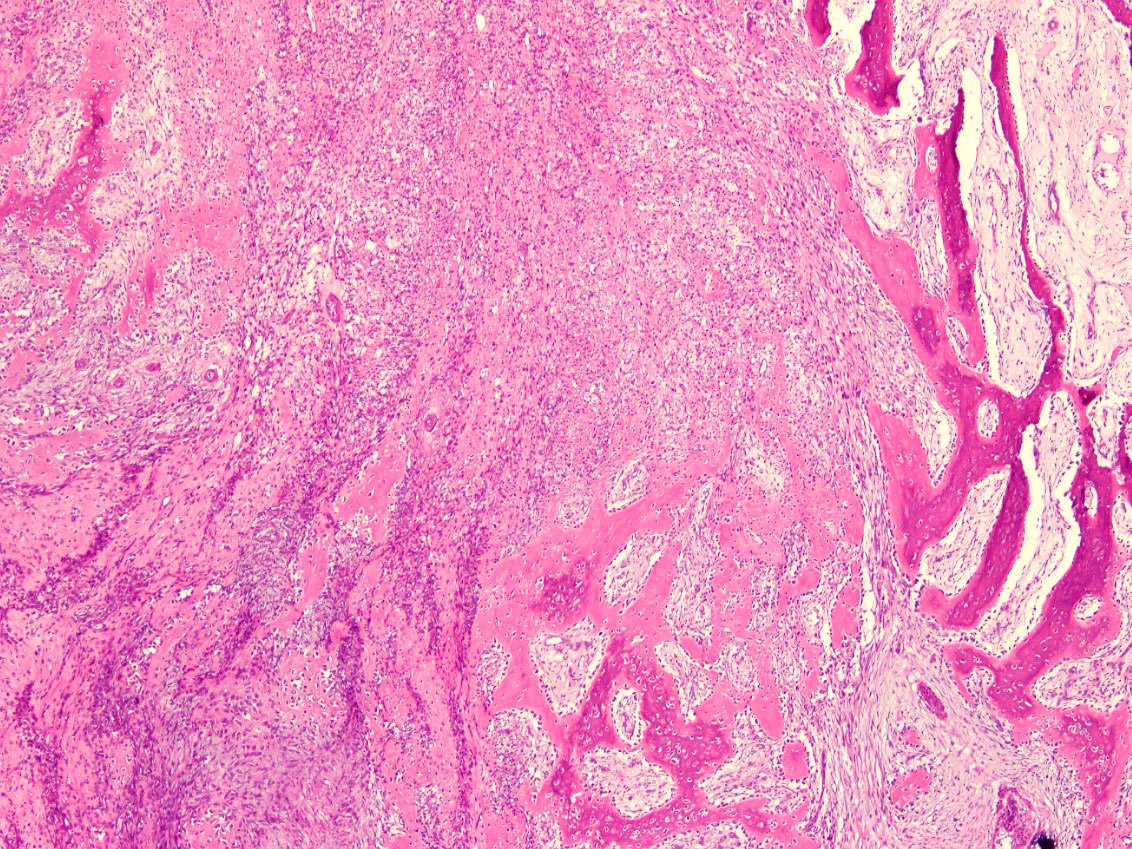

- Histologically, zonal pattern is characteristic with different degrees of cellular differentiation (inner zone, intermediate zone and peripheral zone)

- Peripheral zone:

- Osteoid undergoes calcification and leads to lamellar bone formation

- Islands of mature or immature cartilage may be present

- Extreme periphery / margin shows mature bone with osteoblastic rimming and little to no pleomorphism

- Late, mature stage (> 8 weeks):

- Mass is mostly composed of mature bone

- Very old lesions show only lamellar bone separated by fibrovascular stroma, mimicking osteoma

Microscopic (histologic) images